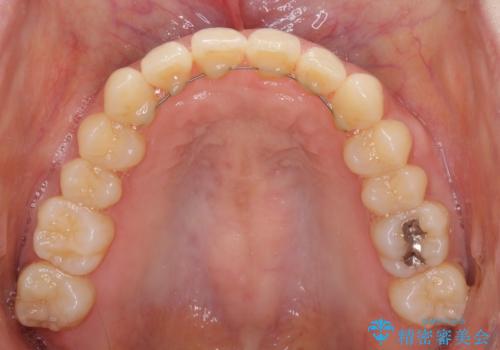

インビザラインによるディープバイトの改善

- 口元の前突感と深い咬み合わせ(ディープバイト)を気にして来院された患者様です。

インビザラインによる上下歯列の遠心移動(後方移動)と、それに伴う近心傾斜(前方傾斜)の改善により、口元の突出感とディープバイトを改善することとしました。

前歯のデコボコを最も気にしていましたが、咬み合わせが深く歯ぎしりが自由にできない点を指摘すると、常に食いしばってしまうことも悩みであることが分かりました。

咬合状態が大きく変化したため、治療後半では咬み合わせの位置が定まらなくなりました。上下の前歯に後戻り防止用のワイヤーを装着し、奥歯の咬合をフリーにしたことで1ヶ月ほどで咬み合わせが定まりました。